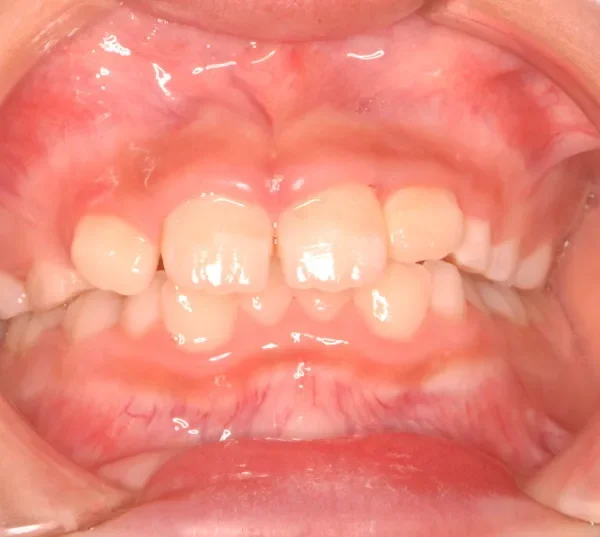

初診時年齢 小学校3年生 (男性) 主訴 前歯がゆがんでいる・ガタガタ

診断名 叢生・交叉咬合 装置名

上下の幅が狭くガタガタに生えています。

初診